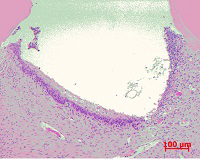

歯科治療の一例

提携 歯科技工所への発注 口腔外科疾患に対する処置

歯科口腔外科用器具による処置 歯肉処置の例

口腔外科に準じた処置 インプラントの埋入手術(上顎)